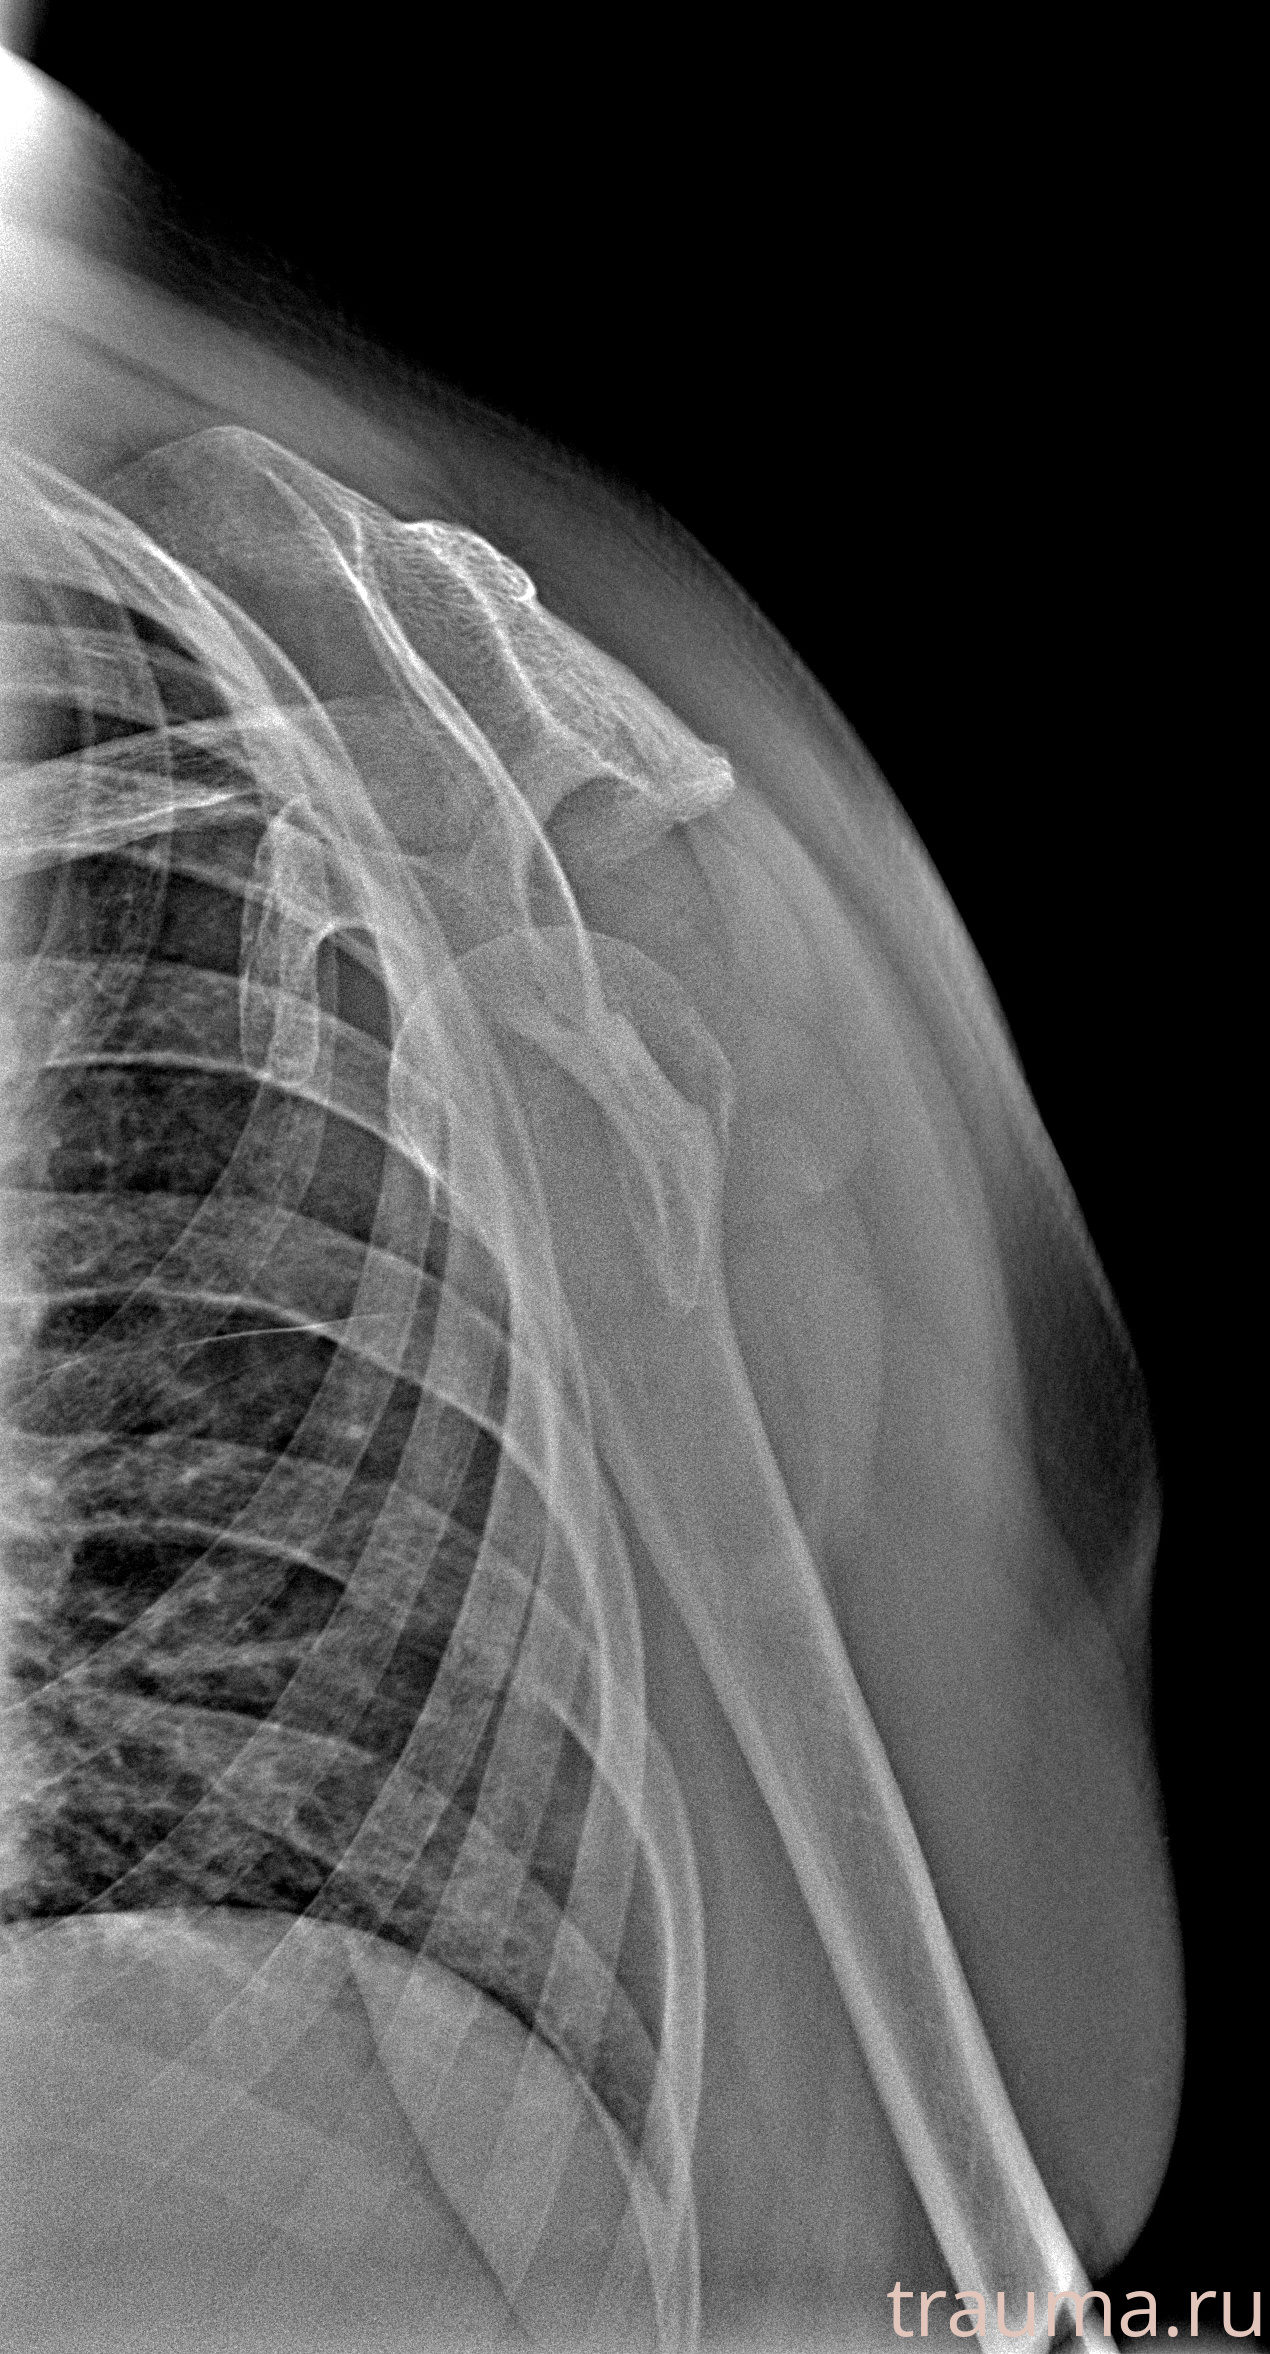

Рентген на дому: по вашему адресу приезжает врач-рентгенолог, травматолог-ортопед с мобильным рентгеновским аппаратом, проводит диагностику травмы или заболевания, делает необходимые рентгенограммы, дает рекомендации по дальнейшему лечению. Получить качественные снимки в домашних условиях возможно благодаря уникальной методике, разработанной МосРентген Центром для института  Склифосовского

при переломе шейки бедра и пневмонии от компании МосРентген Центр - партнера Института имени Склифосовского